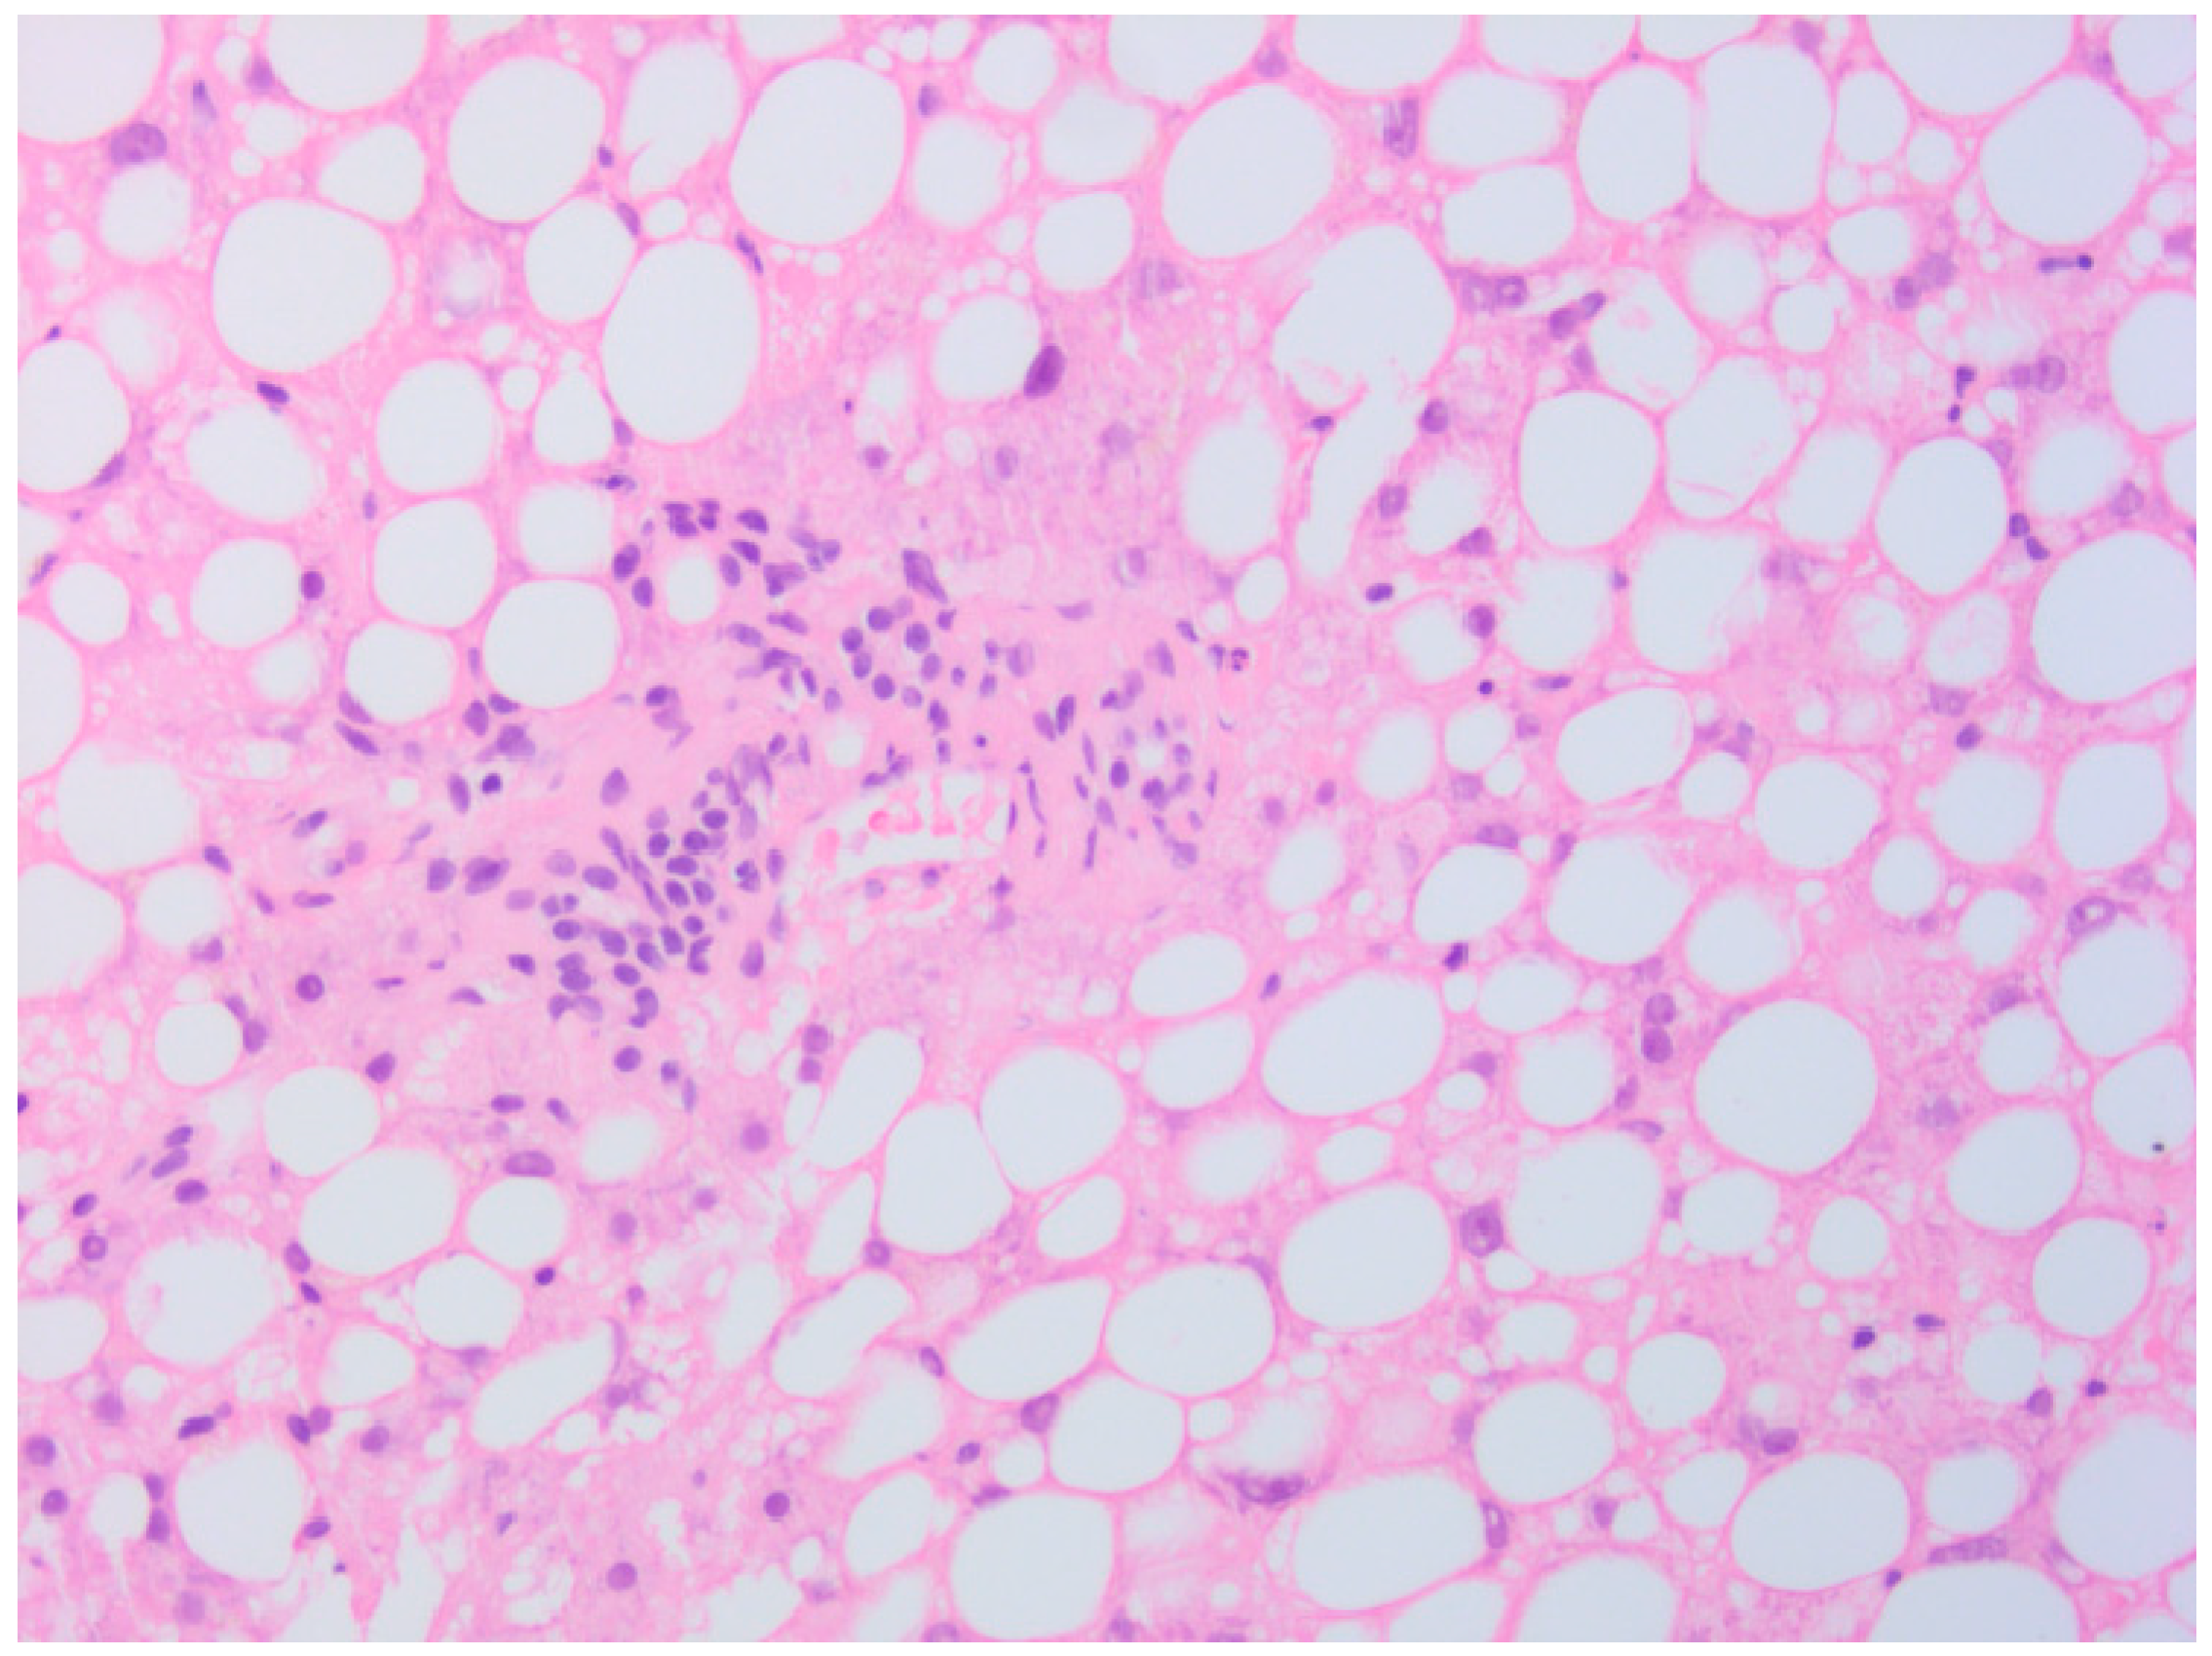

2. Case Presentation